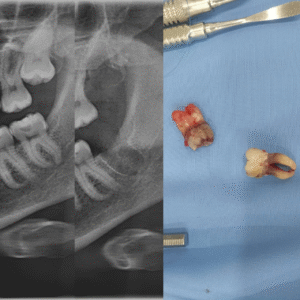

Tiểu phẫu thuật răng khôn

Tiểu phẫu thuật răng khôn hạn chế dùng thuốc, kĩ thuật hiện đại giúp giảm đau, giảm sưng, nhanh lành thương.

Tiểu phẫu răng khôn mọc kẹt và chân cong, dài